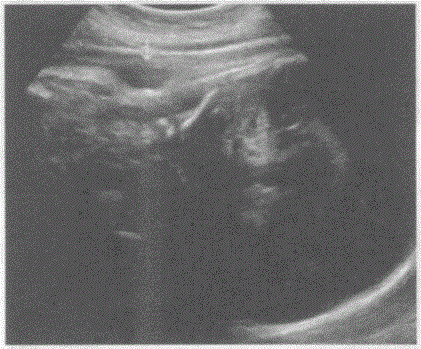

问题 临床资料:女,31岁,孕38周。 超声综合描述:胎儿颈部皮肤见"U"形压迹,CDFI:内见动静脉血流信号,PW:呈动、静脉频谱。见下图及彩图。 {图1} 超声提示:

选项 A.宫内晚孕单活胎脐带绕颈2周 B.宫内晚孕单活胎脐带绕颈1周 C.宫内晚孕单活胎脐带绕颈3周 D.宫内晚孕单活胎脑脊膜膨出

答案 B